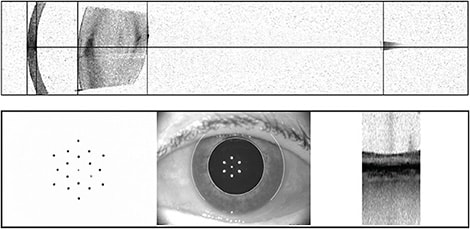

- Biometry. IOL biometers have become much more advanced in recent years, allowing surgeons to better rely on the biometers’ measurements. The latest biometers can obtain an accurate axial length of nearly all eyes except those with the densest of cataracts, thus reducing the need for manual A-scan measurements. Advancements in keratometry have improved outcomes, with current biometers offering anterior and posterior corneal curvature measurements. In addition to offering more accurate results, these machines also give us more information — sometimes more than we know what to do with. Some under-utilized but useful parameters include the light reflex analysis of the ocular surface and the rudimentary macular OCT shown by the IOLMaster 700 (Zeiss, Figure). Like topography, biometry can change dramatically once a dry ocular surface is treated appropriately.

Figure. Patient images from the Zeiss IOLMaster 700. Bottom right: 1-mm macular OCT image. Bottom left: Keratometry image. Note irregularity of spots in this patient with ocular surface disease. These improved upon treatment, and the patient was retested prior to IOL type/power determination. - Astigmatism correction plan. Surgeons differ in their approach to selecting the appropriate type and degree of astigmatism correction for their patients. Three main parameters are usually compared: the topography, the biometer’s predicted K values and the manifest refraction. If these all agree on the amount and axis of astigmatism, the decision becomes simple. If they differ, the surgeon must decide which parameters to rely on or whether repeat measurements should be done. It is important to not rely too heavily on the manifest refraction because this includes lenticular astigmatism, which will be eliminated with cataract surgery. Critically evaluating postoperative residual astigmatism and comparing it with preoperative predictions can be a valuable exercise that allows the surgeon to tailor future treatment decisions.